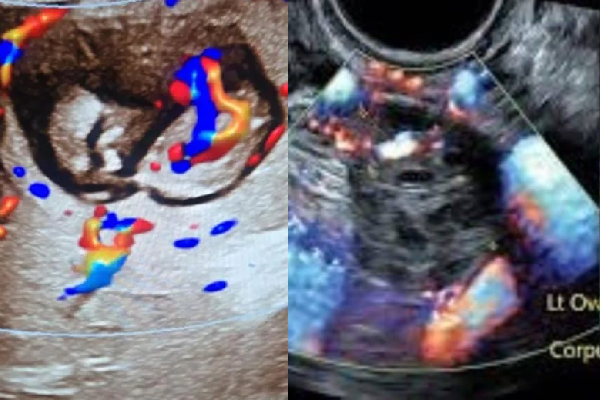

ஆனால் மருத்துவர்கள் அதனை பார்த்து அதிர்ச்சியடைந்துள்ளனர். காரணம் கர்ப்பப்பை காலியாக இருந்துள்ளது. கருவானது கல்லீரலில் வலது மடலில் உருவாகியுள்ளது.

கர்ப்பப்பைக்கு வெளியே கரு உருவாகும் இந்த அரிய மருத்துவ நிலை, இன்ட்ராஹெபடிக் எக்டோபிக் கர்ப்பம் (Intrahepatic Ectopic Pregnancy – IEP) என்று அழைக்கப்படும்.

கிடைக்கக்கூடிய தரவுகளின்படி, இது இந்தியாவின் முதல் இன்ட்ராஹெபடிக் எக்டோபிக் கர்ப்பமாக இருக்கலாம். கரு கர்ப்ப காலத்தில் தோராயமாக 12 வாரங்கள் அளவிடப்பட்டது.

மிகவும் குறிப்பிடத்தக்க வகையில், ஸ்கேன் செயலில் உள்ள இதயத் துடிப்புகளை உறுதிப்படுத்தியது, கரு உயிருடன் இருப்பதை நிறுவியது. அதே வேளையில், மிகவும் அரிதான, அதிக ஆபத்துள்ள கர்ப்பத்தை எதிர்கொள்கிறோம் என்பதை உணர்ந்தோம்” என்று கூறினார்.